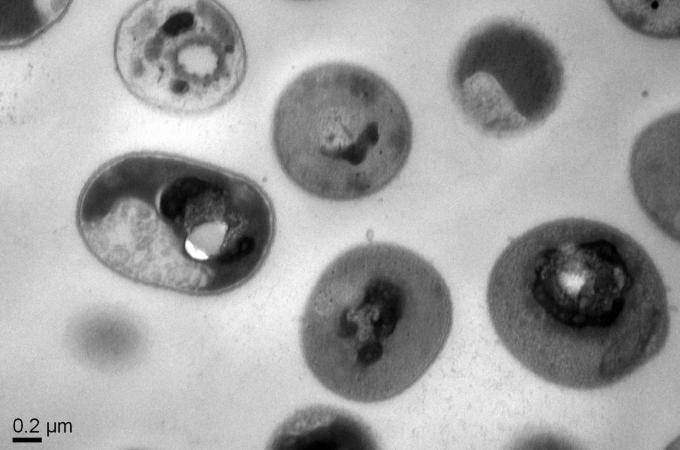

Nová zbraň: Syntetický polymer zabíjí rezistentní bakterie zevnitř